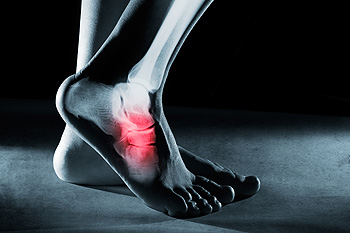

Why Visiting a Podiatrist for an Ankle Sprain Is Important

When the ligaments that hold the ankle in place and connect the bones together become overstretched or torn, an [ankle…